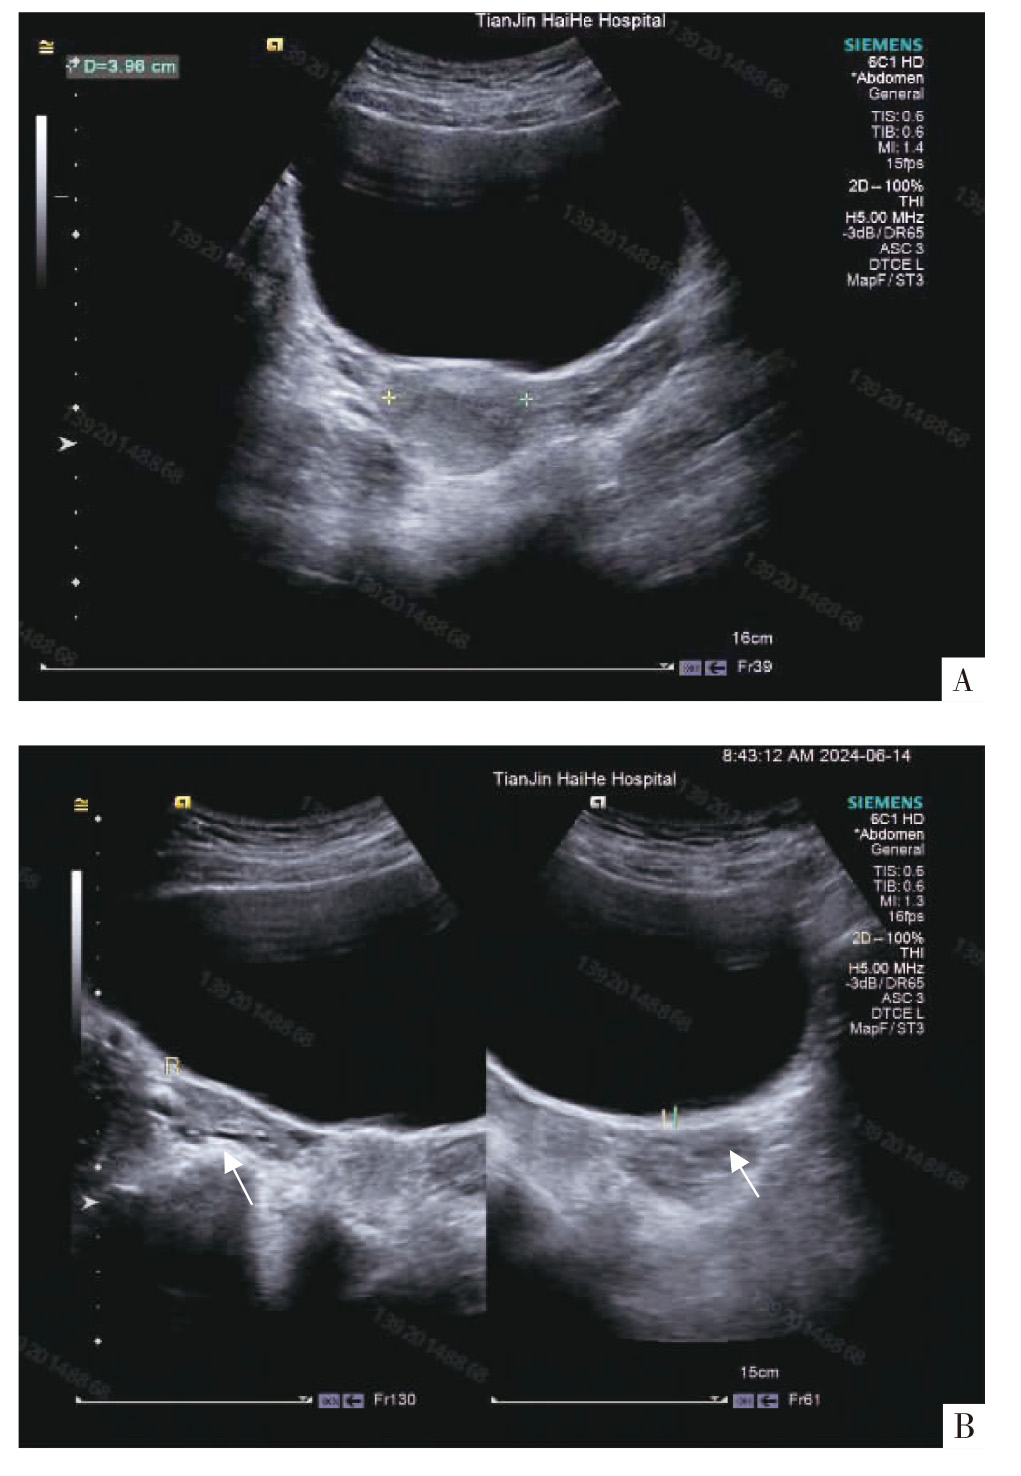

自发性卵巢过度刺激综合征(spontaneous ovarian hyperstimulation syndrome,sOHSS)多数发生于妊娠期,非妊娠期(sOHSS)极其罕见。因该疾病缺乏促排卵病史,重度、极重度患者通常合并胸腹水,影像学表现难以与卵巢肿瘤区分,因此,及时作出诊断十分困难。报告1例罕见的非妊娠期重度sOHSS病例,该患者为20岁女性,因咳痰、恶心、呕吐等症状就诊,经检查发现双侧胸腔积液及盆腔肿物,后转入妇科进一步诊治。通过影像学检查及实验室检测,排除卵巢恶性肿瘤等其他疾病后,结合患者月经不规律及卵巢影像学表现,确诊为sOHSS。在治疗上采取对症支持治疗,包括静脉补液、纠正贫血、胸腔引流等措施,患者病情逐渐好转,最终康复出院。sOHSS诊断困难且临床表现多样,临床医生在面对类似症状时需警惕sOHSS的可能,避免误诊及过度治疗。

Spontaneous ovarian hyperstimulation syndrome (sOHSS) mostly occurs in pregnancy, and sOHSS in non-pregnany is extremely rare. Timely diagnosis is difficult due to the lack of ovulation induction history, the usual combination of hydrothorax and ascites in patients with severe and very severe disease, and difficulty in distinguishing the imaging manifestations from ovarian tumors. We report a rare case of severe sOHSS in non-pregnancy, a 20-year-old female who presented to the hospital with coughing, nausea, and vomiting, and was referred to gynecology department for further management after examination revealed bilateral pleural effusions and pelvic masses. Through imaging examinations and laboratory tests, other diseases such as ovarian malignant tumors were excluded, and the diagnosis of sOHSS was confirmed by the combination of irregular menstruation and ovarian imaging manifestations, sOHSS was treated with symptomatic supportive therapy, including intravenous rehydration, correction of anemia, and thoracic drainage, etc., and the patient′s condition gradually improved and she was eventually discharged from the hospital. sOHSS is difficult to diagnose and has a variety of clinical manifestations, so clinicians need to be vigilant about sOHSS when faced with similar symptoms to avoid misdiagnosis and over treatment.